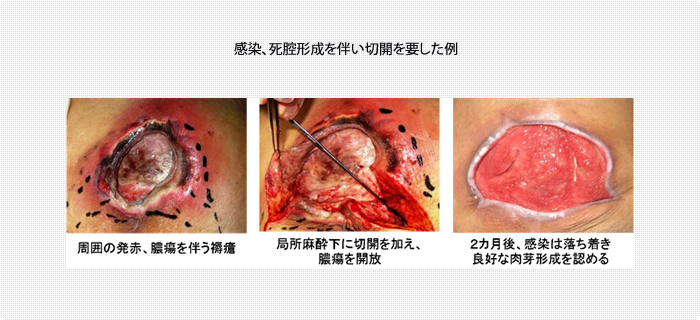

褥瘡の「創縁」「創面」の性状を把握しよう 2ページ目 :日経DI。

慢性期褥瘡の局所治療局所治療の概要褥瘡辞典 for MEDICAL PROFESSIONAL医療関係者向け情報マルホ株式会社。

⑤深い褥瘡攻略の道標 ”TIME+α”のE 創部辺縁の段差 :難関攻略!褥瘡ポケットを治す秘策とは!? -皮膚科専門医が伝授!医療従事者のための高齢者皮膚トラブル対策講座。

褥瘡と難治性潰瘍についてとその治療法について横浜市立大学附属病院。

褥瘡のポケット形成について - 東御市民病院・東御市立みまき温泉診療所・東御市立助産所とうみ。

褥瘡のポケット形成について - 東御市民病院・東御市立みまき温泉診療所・東御市立助産所とうみ。

⑤深い褥瘡攻略の道標 ”TIME+α”のE 創部辺縁の段差 :難関攻略!褥瘡ポケットを治す秘策とは!? -皮膚科専門医が伝授!医療従事者のための高齢者皮膚トラブル対策講座。